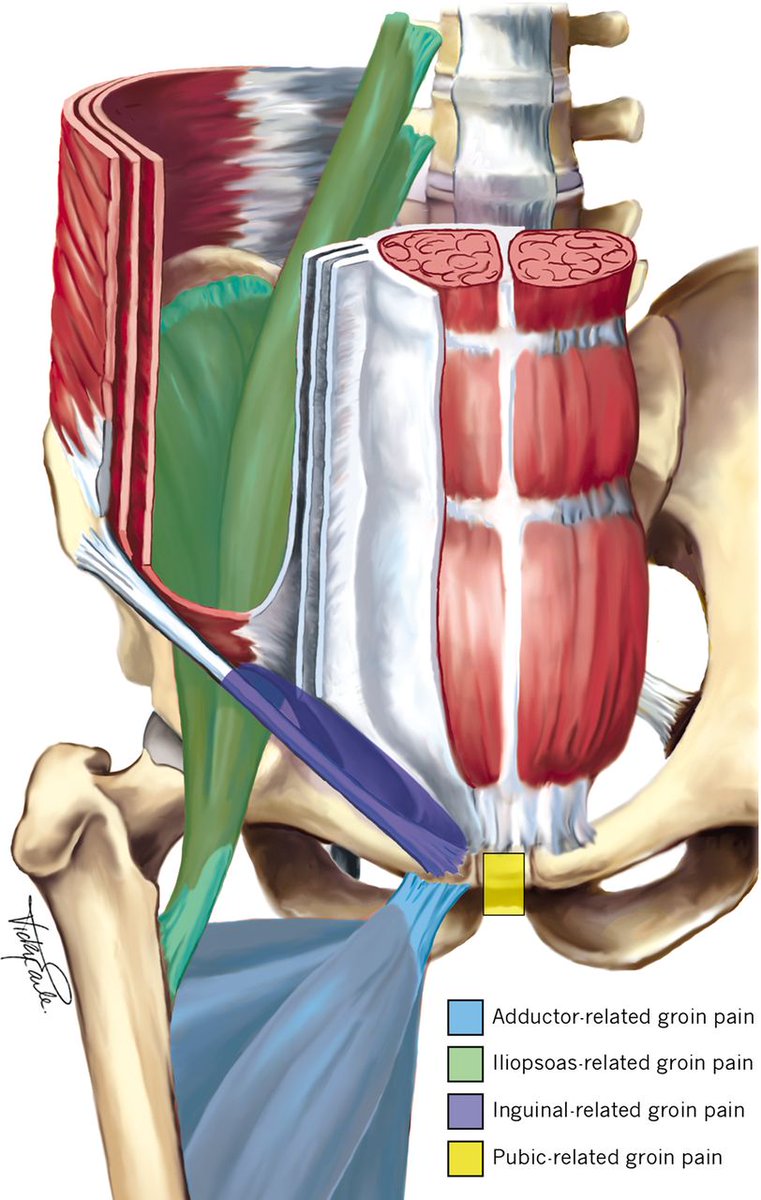

🆕 #AspetarTuesdayLecture 🎯 Contemporary Evidence for the Physiotherapy Management of Hip Pain. 🗣️By - Professor Dr Joanne Kemp 🔗Full Video 👉 youtu.be/jJ4M-W2-rEE 📢📢 Register to attend live sessions of Aspetar’s Tuesday Lecture Series 👉 bit.ly/3ZsySit

🆕"This study investigated if an 8-week ⬆️ volume Adductor Strength program protocol was more effective than a ⬇️ volume protocol in enhancing and maintaining isometric hip adduction strength in female ⚽️ players" 👉Solveig Thorarinsdottir Roald Bahr et al, 2025 🇳🇴 📂onlinelibrary.wiley.com/doi/10.1111/sm…

🆕"This review analyzed the existing research on hip adductor strength testing, highlighting the importance of developing clear guidelines for its application” ➡️Essential for effective monitoring & injury prevention in ⚽️ 👉José María Oliva Lozano et al, 2025 🇪🇸 📂thieme-connect.de/products/ejour…